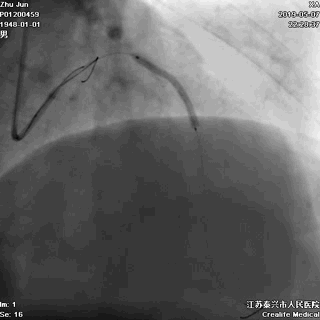

非顺应性球囊高压后扩,保证STENT充分贴壁

大一号球囊高压扩张近段STENT

手术即刻效果完美,患者存活